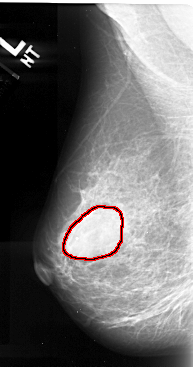

A_1061_1.LEFT_CC

FILE: A_1061_1.LEFT_CC.OVERLAY

TOTAL_ABNORMALITIES 1

ABNORMALITY 1

LESION_TYPE MASS SHAPE IRREGULAR MARGINS ILL_DEFINED

ASSESSMENT 4

SUBTLETY 2

PATHOLOGY MALIGNANT

TOTAL_OUTLINES 1

BOUNDARY